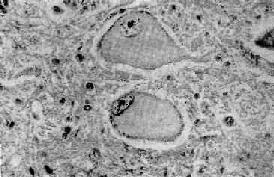

一、神经元与胶质细胞反应(一)神经元 神经元是中枢神经系统的基本结构和功能单位,由细胞体和胞突(树突、轴突)构成。其数目估计在百亿以上。神经元常见的病变为: 1.中央性Nissl小体溶解(central chromatolysis)这是一种可逆性变化,病因一旦去除,就可恢复正常,如病变继续发展,则可导致细胞的萎缩和死亡。常见的病因有病毒感染(如脊髓灰质炎病毒)、维生素B属缺乏、坏血病和神经元与轴突断离。病变表现为神经细胞肿胀,丧失典型的多极形状而变为圆形,胞核偏位,胞浆中央的Nissl小体崩溃成为细尘状颗粒,进而完全溶解消失,或仅在细胞周边部有少量残余。胞浆着色浅而呈苍白均质状(图16-1)。

图16-1 中央Nissl小体溶解 神经细胞肿胀,胞核偏位,Nissl小体仅见于细胞周边部 切断实验动物的轴突后,相关的神经细胞即发生典型的中央性Nissl小体溶解,此现象又称轴突反应。此时神经细胞粗面内质网的核蛋白体解聚,成为游离核蛋白体,蛋白质合成加快,因此认为其与轴突再生有关。 2.神经元急性坏死缺血、缺氧、严重急性中毒或感染可引起神经元的死亡。表现为神经细胞核固缩,胞体缩小变形,胞浆Nissl小体消失,呈深伊红色,称为红色神经细胞。如细胞坏死后的酶性分解过程继续发展,则可导致细胞溶解和消失。隐约可见轮廓的死亡细胞称为鬼影细胞(ghost cell)。因缺血引起的神经细胞坏死最常见于大脑皮质的锥体细胞和小脑蒲肯野(Purkinje)细胞(图16-2)。